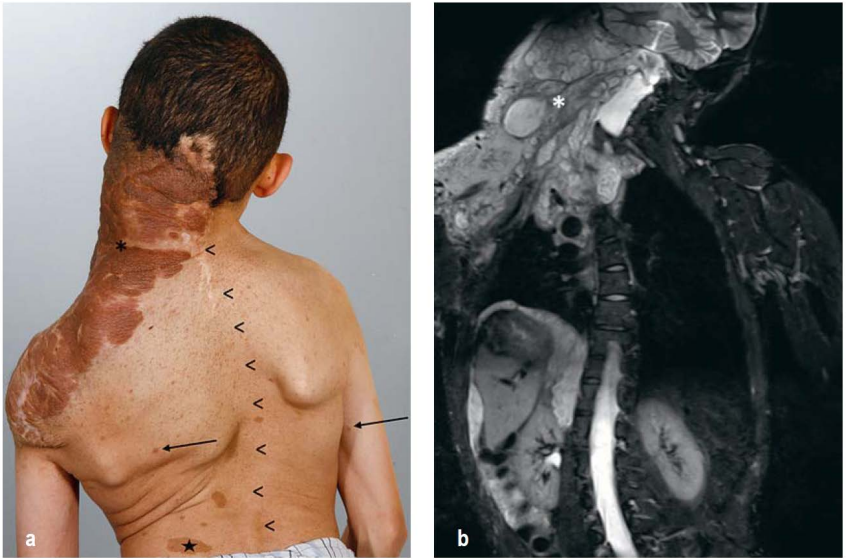

По данным многочисленных российских и зарубежных публикаций, в 2023–2024 годах отмечался значительный рост внебольничных пневмоний у детей, при этом в Российской Федерации выявлены

многочисленные очаги групповой заболеваемости пневмонией, вызванной Mycoplasma pneumoniae, с преимущественным вовлечением в эпидемиологический процесс детского населения. В клинической картине респираторного микоплазмоза отмечается поражение различных этажей дыхательных путей с преимущественным вовлечением в патологический процесс нижних отделов, развитием бронхита и пневмонии, часто с синдромом бронхиальной обструкции на фоне мукостаза. При этом сведения о внереспираторных проявлениях данной инфекции в литературе малочисленны. Из внереспираторных проявлений наиболее часто отмечается поражение кожи в виде различных высыпаний, эрозивно-язвенные изменения слизистых, так называемые мукозиты, поражение сердечно-сосудистой системы с развитием кардитов, нарушений ритма, атритов. К более редким проявлениям относится гемолитическая и апластическая анемия, к наиболее тяжелым – поражение центральной нервной системы: энцефалиты, миелиты микоплазменой этиологии. В статье приведен клинический пример течения инфекции, вызванной Mycoplasma pneumoniae, у ребенка 10 лет с развитием тяжелого мукозита, протекающего в сочетании с поражением респираторного тракта и рядом других проявлений.